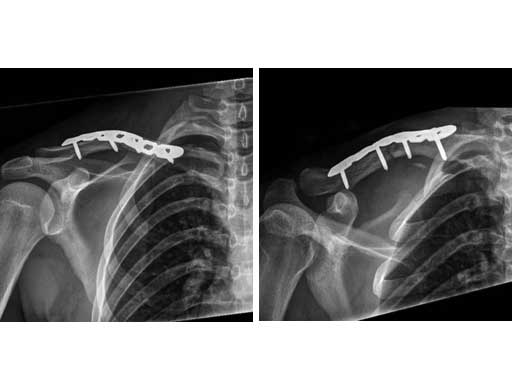

Fig 4ab X-rays 9 months postoperatively.